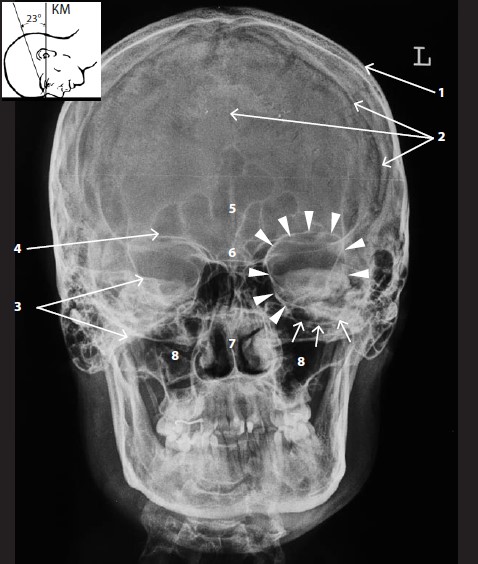

Хорошо видны кости свода черепа (1) и черепные швы (2). Изображение пирамид височных костей (3) наслаивается на глазницы (4), из-за чего вход в глазницу, обозначенный маленькими треугольными стрелками, и особенно подглазничный край (маленькие стрелки) прослеживаются фрагментарно. Достаточно отчетливо видна верхняя глазничная стенка. Кроме того, на снимке визуализируются лобные пазухи (5), решетчатая пластинка решетчатого лабиринта (6), полость носа (7), верхнечелюстные пазухи (8).